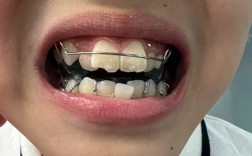

| 螺旋扩弓器(可摘式) | 轻度牙弓狭窄,患者配合度要求高 | 优点:可自行加力,方便清洁;缺点:依赖患者操作,效果稳定性较差。 |

- 加力与配合:严格遵循医嘱加力(如RME每日2次,每次0.25mm),避免过度用力导致牙齿或牙周损伤;可摘式扩弓器需每日佩戴≥20小时。